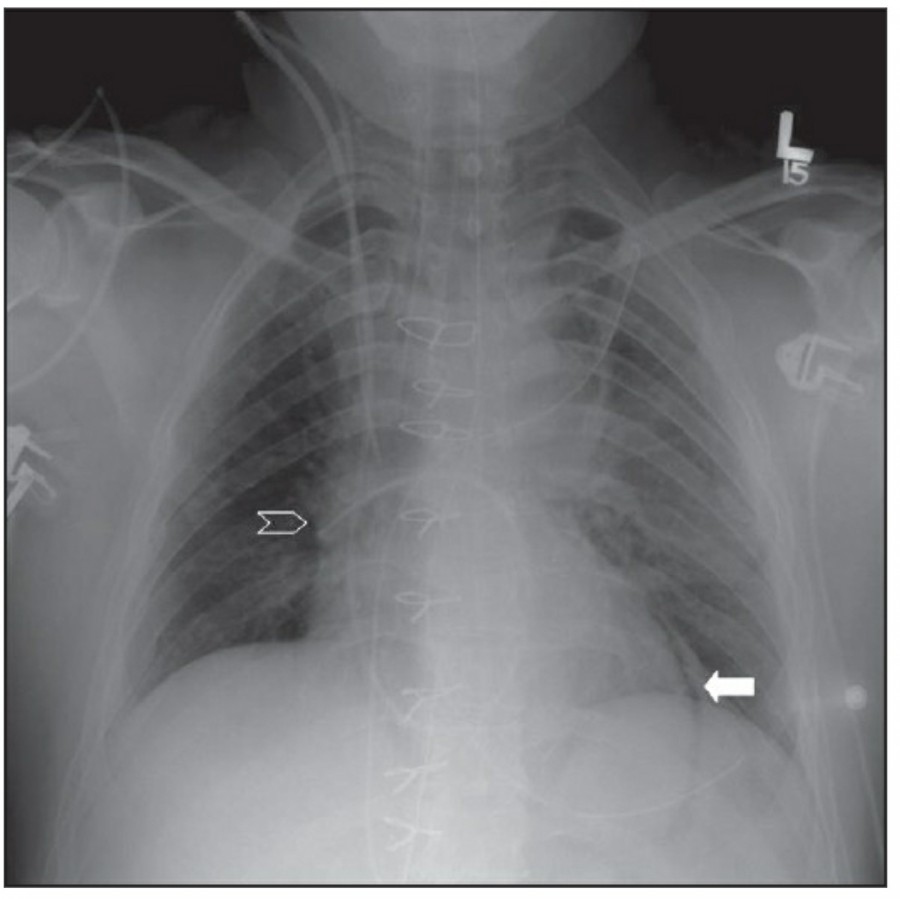

Pneumothorax

공기는 nondependent position으로 위치하므로, X ray상에서는 환자 자세에 따라 다르게 나타난다. Erect position에서 공기는 lung의 apicolateral surface에 위치하고 얇고 하얀 pleural line이 나타나며 그 뒤로 lung marking이 보이지 않는다.

하지만 pleural line 뒤로 lung marking이 존재한다고 해서 pneumothorax를 배제할 수 없다. Pneumothorax의 진단은 특히 parenchymal disease가 있을 때 진단하기 힘든데, 이는 compliance의 변화 때문에 collapse가 잘 안 되기 때문이다. Skin fold가 pneumothorax와 비슷하게 보이기도 한다.

중환자에서 pneumothorax의 진단은 종종 supine radiograph에서 내릴 수 있다. Supine position에서 공기는 anteromedial 방향으로 모이게 되는데, apical air collection이 있을 경우 large pneumothorax가 있음을 시사한다. 공기는 lung과 diaphragm 사이의 subpulmonic location에 trap 되어 있을 수도 있다. 공기가 costophrenic sulcus로 anterolateral extension 될 경우, 이 costophrenic sulcus의 radiolucency를 증가시키는데, 이를 deep sulcus sign이라고 한다. Subpulmonic pneumothorax의 다른 특징으로 diaphragm의 superior surface와 IVC 윗부분이 뚜렷하게 보일 수 있다.

중환자에서 tension pneumothorax의 진단은 매우 힘들다. ARDS와 같은 lung의 병리적인 기전이 lung compliance를 감소시킴으로써 total lumg collapse를 막는다. 또한 tension pneumothorax의 특징인 mediastinal shift가 PEEP으로 인해 나타나지 않을 수 있다. Chest X ray 상에서 tension pneumothorax는 hemidiaphragm의 depression이나 heart border, SVC, IVC의 이동으로 나타날 수 있다.